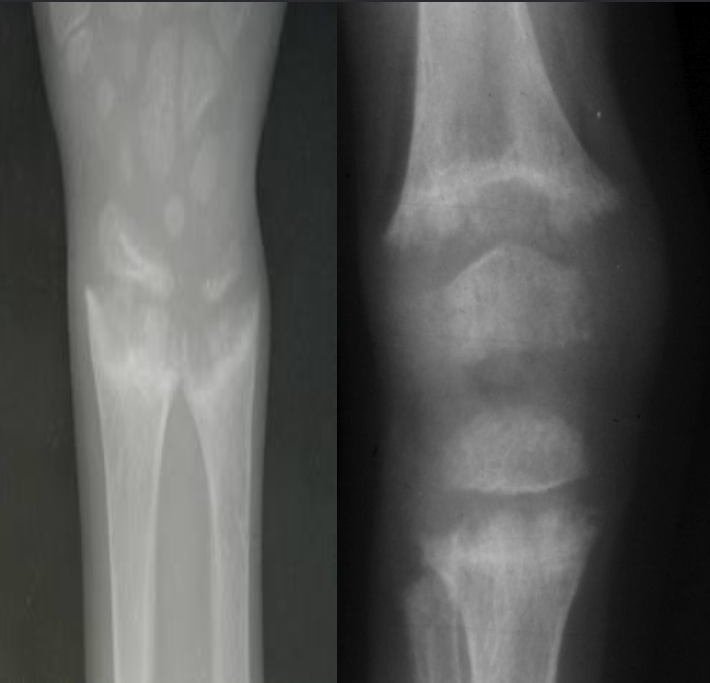

A. Give ONE radiological sign for an abnormal

wrist/knee.

B. What is the most likely diagnosis in the given image? Rickets

- Growth plate is widened

- Metaphysical margin is cupped and irregular